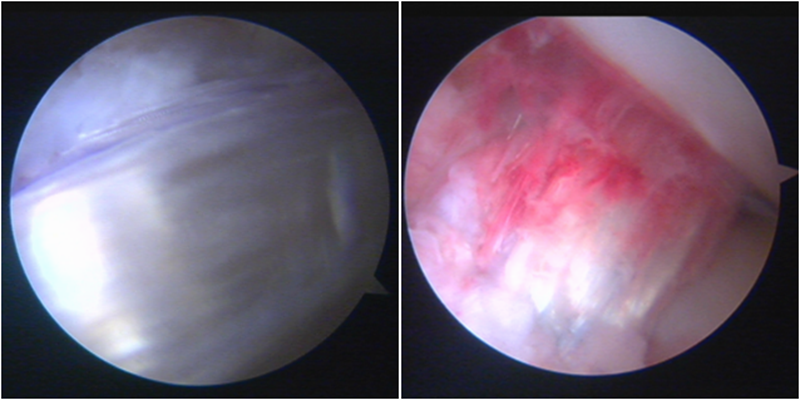

送止血带后韧带表明血管膜

术后MRI